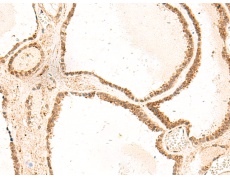

ELISA, IHC |

IHC positive control: |

Human thyroid cancer |

IHC Recommend dilution: |

50-300 |